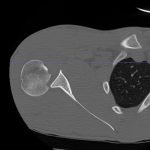

Radiographs demonstrated posterior displacement of the humeral head on the “Y” view (see white arrow) and widening of the glenohumeral joint space on anterior-posterior view (see red arrow). The findings were consistent with posterior dislocation and a Hill-Sachs type deformity. Sedation was performed and reduction was attempted using external rotation, traction counter-traction. An immediate “pop” was felt during the procedure. Post-procedure radiographs revealed a persistent posterior subluxation with interlocking at posterior glenoid. CT revealed posterior dislocation with acute depressed impaction deformity medial to the biceps groove with the humeral head perched on the posterior glenoid, interlocked at reverse Hill-Sachs deformity (see blue arrow).

Posterior shoulder dislocations are rare and represent only 2% of all shoulder dislocations. Posterior shoulder dislocations are missed on initial diagnosis in more than 60% of cases.1 Posterior shoulder dislocations result from axial loading of the adducted and internally rotated shoulder, violent muscle contractions (resulting from seizures or electrocution), a direct posterior force applied to the anterior shoulder.1 Physical findings include decreased anterior prominence of the humeral head, increased palpable posterior prominence of the humeral head below the acromion, increased palpable prominence of the coracoid, marked limitation of abduction, and complete absence of external rotation with a fixed internal rotation deformity.2 Lesions commonly associated with traumatic posterior subluxation/dislocation are the reverse Hill-Sachs,3 a posterior labral detachment, glenohumeral ligament lesions,4 rotator cuff tears or posterior bony fractures.1 In order to make an accurate diagnosis it is important to obtain adequate x-ray imaging, including a “Y” view.2 Anteroposterior x-rays may show widening of the glenohumeral joint resembling a “light bulb” shape of the humeral head. However, definitive diagnosis is made by the “Y” view which shows the humeral head displaced posteriorly and no longer covering the glenoid fossa6. Irreducible acute posterior dislocation of the shoulder is extremely rare5 and only one other case has been reported in the literature.7